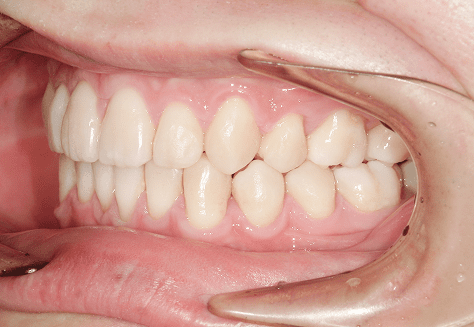

M.U

治療前

治療後

主訴

下の歯が特にガタガタなのが気になる。上の前歯が1本反対になっている。

診断

下顎前突・叢生・反対咬合

年齢/性別

20代/男性

抜歯部位

非抜歯

使用装置

上下インビザライン(PBM使用)

保定装置

ビベラリテーナー

料金

初回資料採得・・・・・・・30,000円

診断料・・・・・・・・・・33,000円

動的治療終了時資料採得・・5,500円 -

基本料金

950,000円

診察料金

5,500円×16回

治療期間

1年7カ月